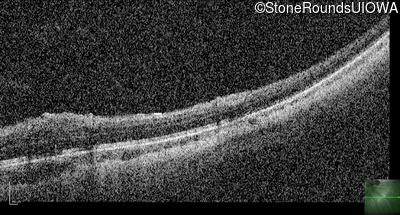

Optical Coherence Tomography - Left - 20/80

Exemplar / OCT Stack